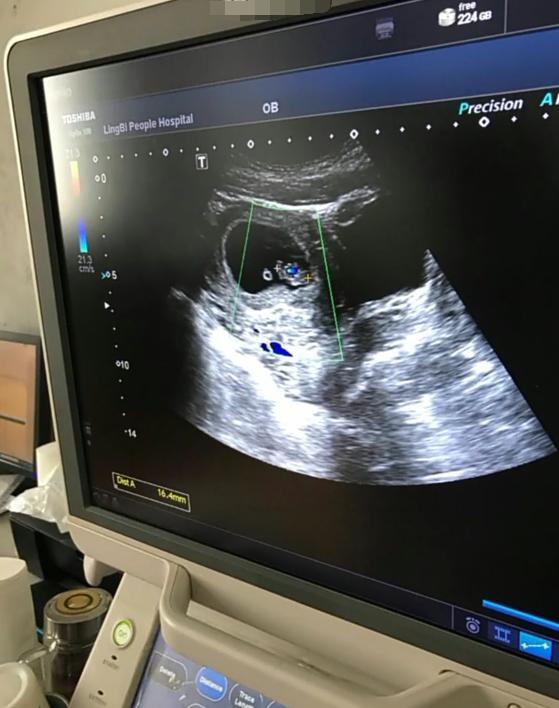

而男宝,生殖器从孕8-9周才开始往男性方向发展,孕10-11周,*丸睾**才开始出现雏形,之后是阴囊产生,直到孕22周,*丸睾**才会慢慢下降,到孕晚期抵达阴囊,形成壶把儿样的生殖器,所以从生殖角度出发,男宝的发育比女宝要慢,可能到孕28周左右才能完全确定,在此期间极有可能因为看不清,误认为是女宝,所以早于孕28周去检查,可能不是特别准确,女翻男也就有可能了。

检查男宝还是女宝,靠的是医生的眼力和经验,但是有时候,宝宝比较调皮,夹着腿不小心就把小jj给隐藏起来,被医生误认为是女宝,所以也容易出现女翻男了。有时候,检查好几次,都被确认为女宝,可是生出来却是男宝,就是这个原理了。而女宝宝出现这种情况的则很少见,但有时候医生会把脐带误认为是小jj,也会发生男翻女的情况,但总体来说,男翻女的概率比女翻男的概率要低一些,很多宝妈总是分享女翻男的经验,很少有宝妈分享男翻女的经验,也就是这个道理了。除了B超,这两项检查才是最准确的: